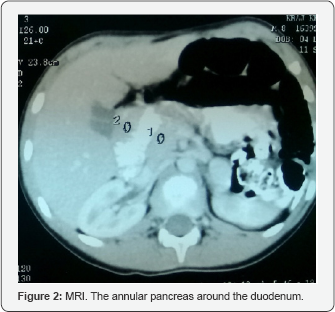

The boy's phenotypic features were consistent with Noonan syndrome. The dermatoglyphs of the boy finger tips and right hand were abnormal. The karyotype was normal. The skeletal age was 6 years of age. Echocardiography did not reveal congenital heart defects. Family history of genetic disorders or congenital malformations was negative. In the opinion of the consulting clinical geneticist the boy presented with Noonan syndrome (Figure 2). The patients has been qualified for surgical intervention due to recurrent vomiting, abdominal pain and the confirmation of duodenal obstruction in the CT and MRI scans.